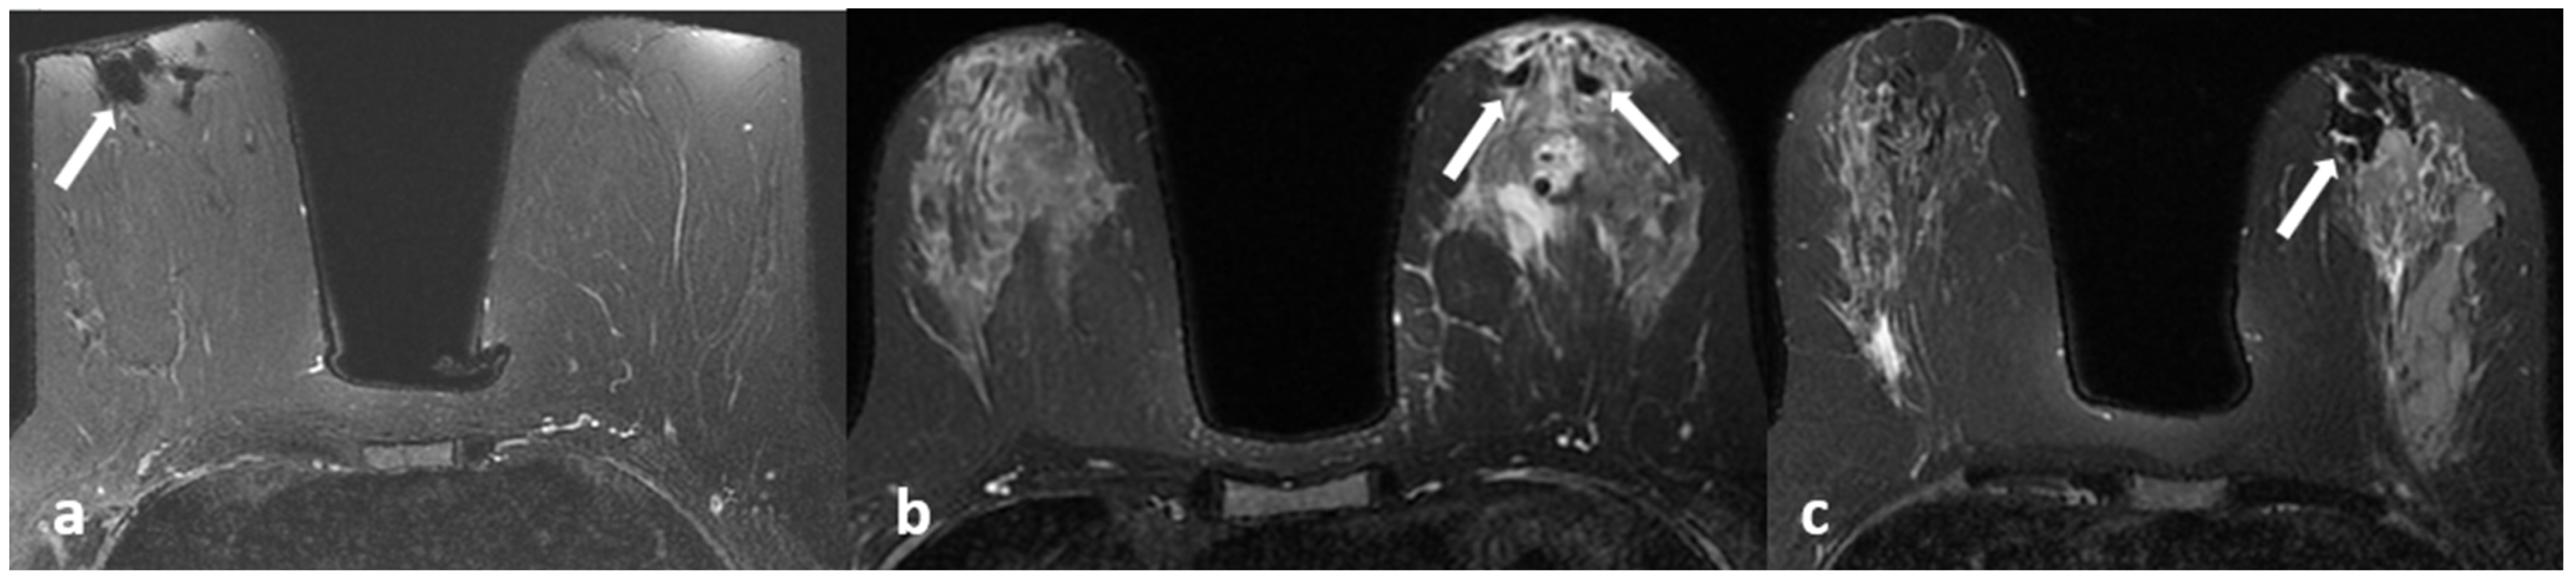

3.1. Non-Enhanced Images

3.2. Contrast-Enhanced Images